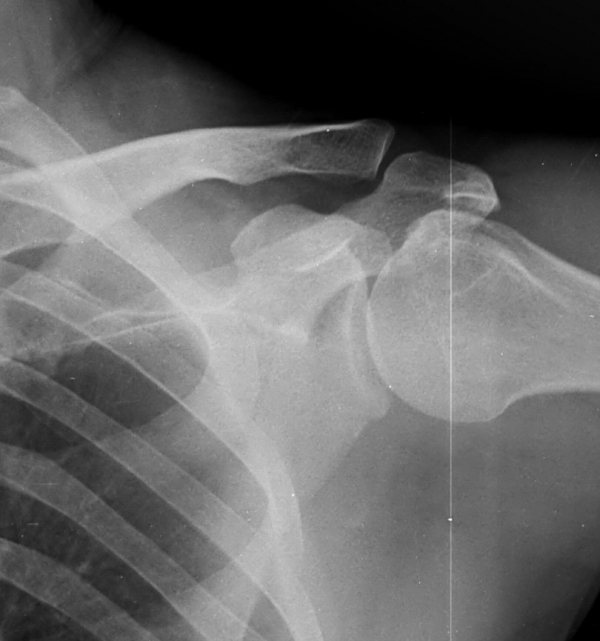

ƯÀÌ °ßºÀ ¾Æ·§¸éÀÇ °æÈ­ ¼Ò°ß ¹× °ßºÀ ¾Æ·¡ ¿¹¸®ÇÑ °ñ±ØÀÌ °üÂûµÊ

±Ø»ó°Ç ÆÄ¿­, Á¡¾×³¶¿°, °ßºÀÇÏ °ñ±Ø

¹æ»ç¼±»çÁøÀ̳ª ÀÚ±â°ø¸í°Ë»ç¿¡¼­ °ñ±ØÀÌ °üÂûµÇ°í ±Ø»ó°Ç ÆÄ¿­ÀÌ ÀÖ´Â °æ¿ì °Ë»ç¿¡¼­ º¸ÀÌ´Â

°ñ±ØÀÌ ±Ø»ç°ÇÆÄ¿­ÀÇ ¿øÀÎÀ̶ó°í ÃßÁ¤ÇÒ ¼öµµ ÀÖ´Ù.  ±×·¯³ª ±Ø»ó°ÇÆÄ¿­ÀÌ Ç¥Ãþº¸´Ù´Â ½ÉÃþ¿¡¼­

´õ ¸¹ÀÌ ¹ß»ýÇϰí Áõ»óÀ» ÀÏÀ¸Å°Áö ¾Ê´Â °ñ±ØÀÌ ¸¹Àº Á¡À» °í·ÁÇÒ ¶§ °Ë»ç¿¡¼­ º¸ÀÌ´Â °ñ±ØÀ»

Ä¡·á(°ßºÀ¼ºÇü¼ú)ÀÇ ´ë»óÀ¸·Î ÇÏ´Â °ÍÀº Çϸ®ÀûÀÎ °áÁ¤ÀÌ ¾Æ´Ï´Ù. ÀÌ È¯ÀÚÀÇ °æ¿ìó·³ ±Ø»ó°Ç